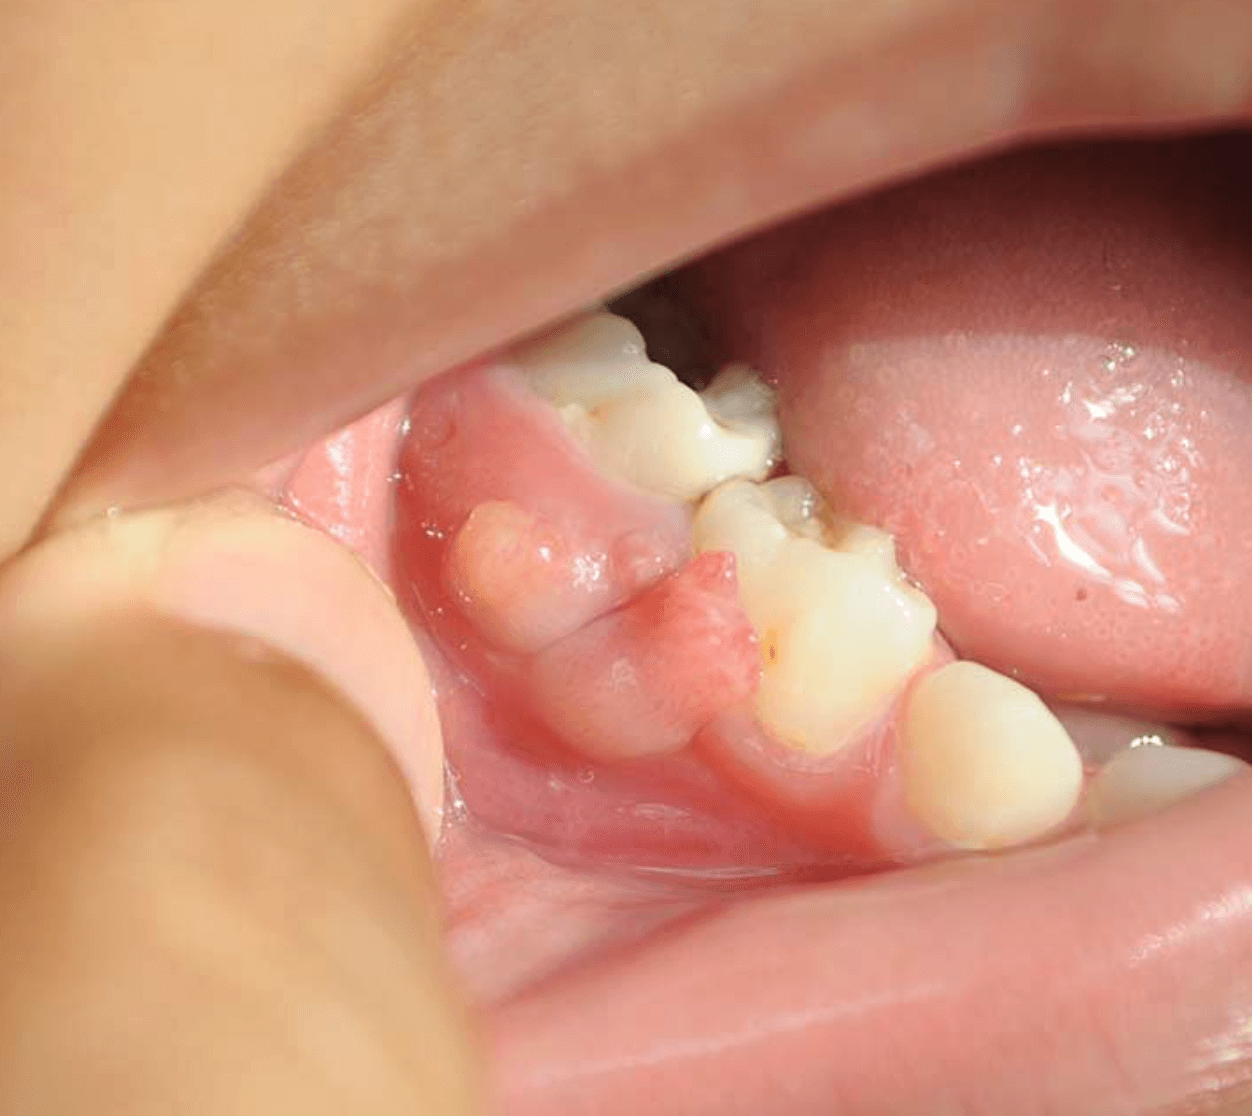

잇몸에 고름주머니가 생기면 최대한 빠르게 치과에 와서 치료를 받는것이 좋습니다. 잇몸 고름주머니는 염증이 생겨 고름이 빠져나가지 못하는 고름이 뼈를 녹여 잇몸이 부풀어 오른경우를 말합니다. 이러한 잇몸 염증 치주 농양 치료법과 비용에 대한 정보를 공유 합니다.

일반적으로 잇몸에 고름이 생기는것을 치주 농양이라고 이야기를 합니다. 이러한 잇몸 고름주머니는 심각한 잇몸 질환 치주염으로 인해 발생할수 있으며, 이로인해 박테리아가 자랄수 있는 고름주머니가 생길수 있습니다.

또한 치석이 너무 많이 쌓이거나 음식물이 주머니에 끼면 고름이 발생하게 되고 이러한 고름이 배출되지 않으면 치주 농양이 형성되게 됩니다. 치주 농양은 인근 치아에 발열과 같은 통증을 유발하고 치아와 잇몸의 뼈를 녹이거나 잇몸을 손상시켜 치아가 흔들리고 빠질수 있습니다.